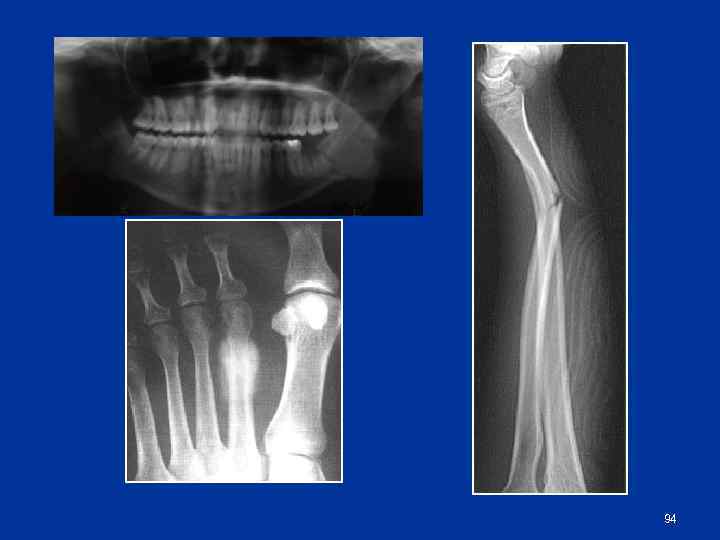

Особенности переломов у детей n n n Эпифизеолиз Поднадкостничные переломы Переломы по типу «зеленой веточки» 93

94